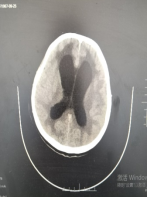

术前影像:CT提示明显交通性脑积水,脑室系统扩大。